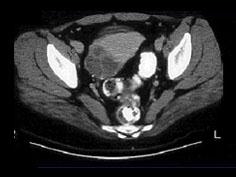

问题 这是一幅绒毛膜癌的CT图片,CT对绒毛膜癌的诊断有那些帮助 ( )

选项 A、可以确诊绒毛膜癌 B、可以与其他滋养细胞疾病鉴别 C、脑部转移灶 D、肝部转移灶 E、发现肺部较小病灶

答案 CDE